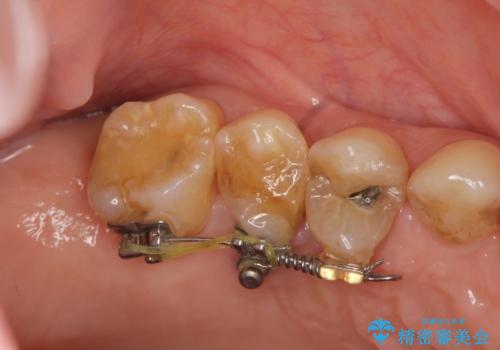

部分矯正を含む 歯周病治療 (再生治療・歯周ポケット除去・MTM・連結補綴)

検査の結果、強い歯ぎしりによる歯の周囲の骨の吸収が認められたため歯槽骨の再生・歯周ポケットの除去・力に対抗する連結補綴・補綴前処置としての小矯正を計画します。

今回連結補綴を行うにあたり、歯周病の問題を解決するために再生療法・歯周ポケット除去手術を、またより歯の神経を保存し力に対抗できる環境を整えるために小矯正を行い精度の高いメタルボンドクラウンを製作することができました。